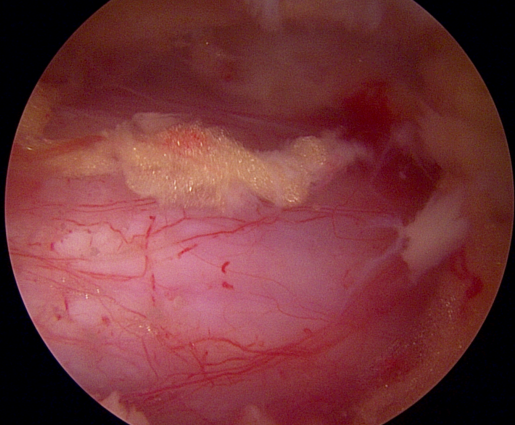

양방향 척추 내시경을 통한 다발성 척추 협착증의 치료 [온종합병원 척추센터 우영하 소장 ]

척추관 협착증은 척추관이 좁아지거나 협착되어 척수나 신경근을 압박하는 상태를 말합니다. 이런 경우, 양방향 척추 내시경이 매우 유용한 치료 수단이 될 수 있습니다.

- 계획: 양방향 척추 내시경은 미세한 카메라와 도구를 사용하여 척수와 주변 신경 구조를 정밀하게 시각화할 수 있습니다. 이를 통해 정확한 진단을 내릴 수 있으며, 각 환자에게 맞는 개별적인 수술 계획을 수립할 수 있습니다.

양방향 척추 내시경은 척추관 협착증과 같은 척추 질환의 치료에 있어서 현대적이고 효과적인 접근법 중 하나로 인정받고 있습니다.